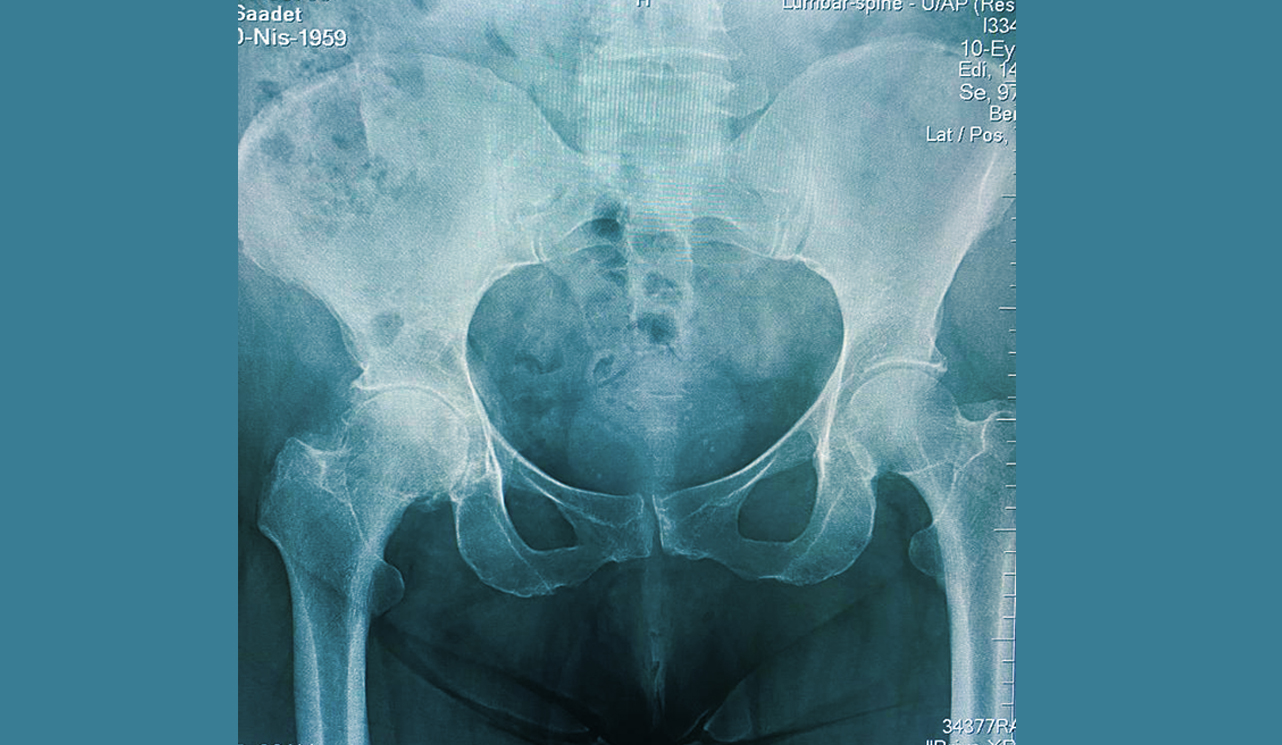

Artoz yani diz kireçlenmesi eklem kıkırdağının dejenerasyonuna eşlik eden kemik dokusunda bir artışla ortaya çıkan bir eklem hastalığıdır. Erkeklerden daha çok kadını etkiliyor. Osteoartrit, yaşlılarda ağrı ve özerklik kaybının en yaygın nedenlerinden biridir.

Kalça eklemi kireçlenmelerini temel olarak ikiye ayırabiliriz. Daha sık karşılaştığımız birinci grupta doğumsal yada sonradan oluşan yapısal bir bozukluk (kalça çıkığı, artrit, travma vb) nedeniyle zaman içinde kalça eklemindeki kıkırdakların aşınması sonucu ortaya çıkan kireçlenmeler yer alırken, ikinci grupta idiyopatik olarak adlandırdığımız sebebi belirlenemeyen kalça kireçlenmeleri yer alır.